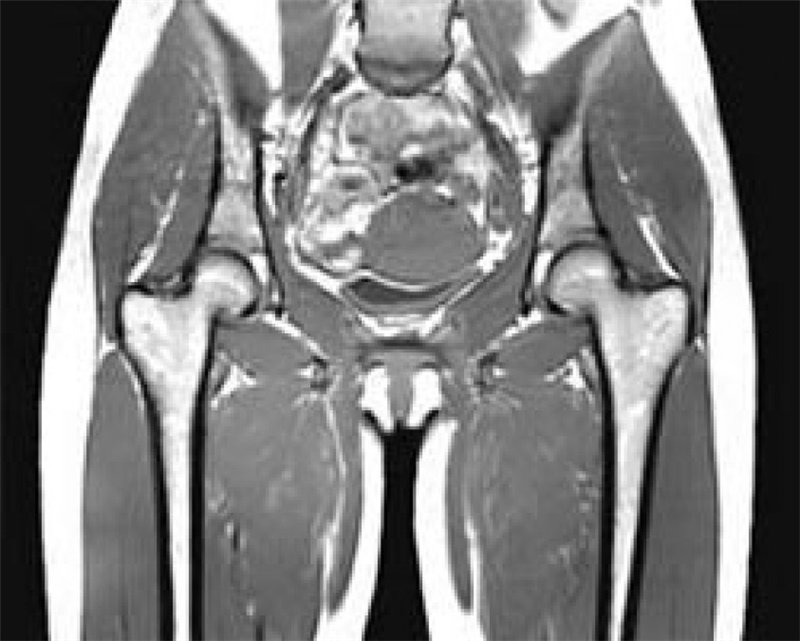

1. Сбор анамнеза.

2. Физикальное обследование.

3. Рентгенография тазобедренных суставов.

4. КТ, МРТ.